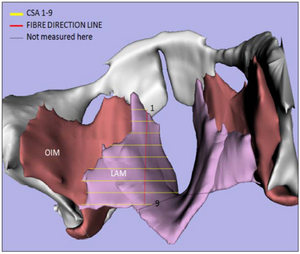

MRI with labeled structures from atlas registered to the CBCT. Registration was carried out with the open source imaging tool 3D Slicer, Version 4.4.0. |